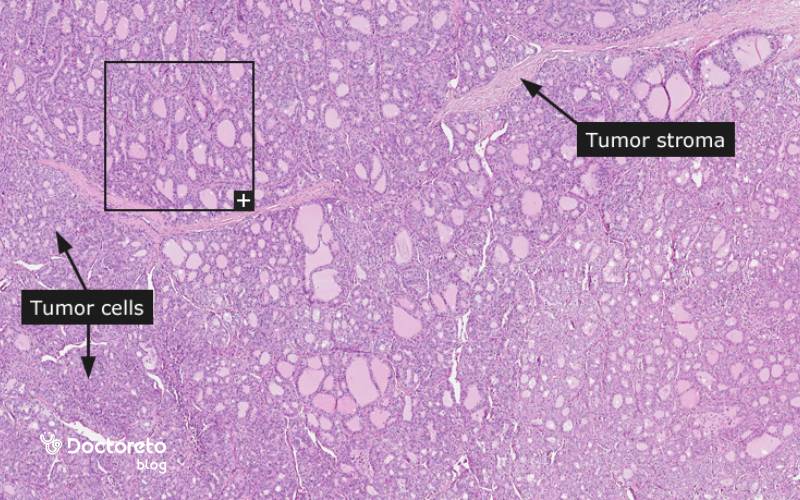

گزارش پاتولوژی معمولاً نوع بافتشناختی (مثلاً پاپیلاری کلاسیک یا نوعهای متغیر)، اندازهٔ دقیق تومور، میزان تهاجم کپسولی، عروقی، حاشیههای جراحی، درگیری غدد لنفاوی و ویژگیهای مولکولی (در صورت بررسی) را ذکر میکند. این جزئیات برای تعیین مرحله و ریسک عود حیاتی هستند. مثلا وجود تهاجم عروقی در فولیکولار یا گسترش خارج تیروئید در پاپیلاری، درمان تکمیلی را محتملتر میکند. هماهنگی گزارش پاتولوژی با یافتههای تصویربرداری و بالینی، تصمیم درمانی را دقیقتر میسازد. تصویر تومور را در نمونه جواب پاتولوژی سرطان تیروئید در زیر مشاهده میکنید.